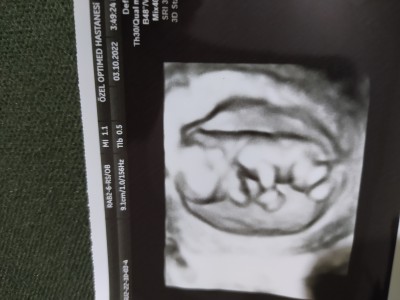

Kızlar diğer taraftan sordum fakat kapatıldı yoruma burdan da sorayım. 13+1 haftalık hamileyim bebeğimin cinsiyetini merak ediyorum yardımcı olabilir misiniz ilk hamileliğim

Erkek gibi göründü bana ama Allah'ın takdiri hayırlısı ile al kucağına rabbim yar ve yardımcın olsun inşallah canım

Sankii erkek..

Kesin sonuç alınca haber ver bana bakalım bana göründüğü gibi erkek mi bebeto

Kız hissettim ben de